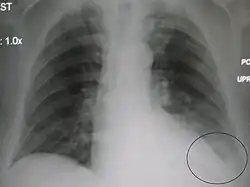

| A parapneumonic effusion (circled), due to a left lower lobe pneumonia. |

A parapneumonic effusion is a type of pleural effusion (accumulation of fluid in the pleural cavity) that arises as a result of a pneumonia, lung abscess, or bronchiectasis.[1] There are three types of parapneumonic effusions: uncomplicated effusions, complicated effusions, and empyema. Uncomplicated effusions generally respond well to appropriate antibiotic treatment.